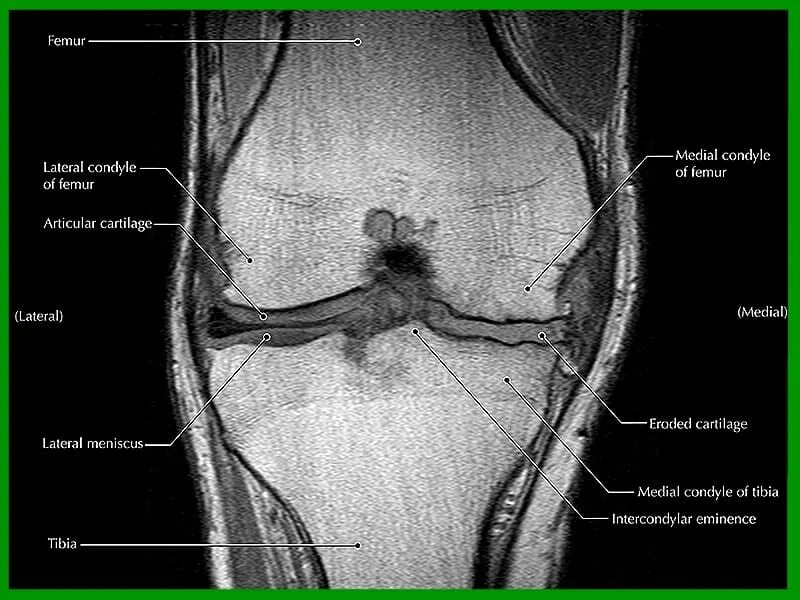

Гонартроз мрт